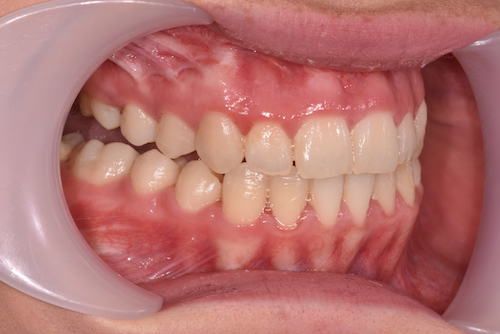

What are the expected benefits of surgery?

- Improved facial appearance

- Improved function – better bite, no pain / trauma on biting

- Straight teeth